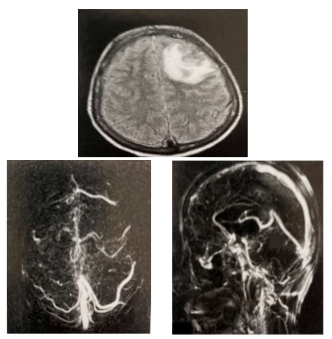

Mulher, professora, 37 anos apresentou crise epiléptica

generalizada em seu trabalho, sendo levada de imediato ao

atendimento médico de emergência. Na admissão, após o

período pós-ictal, paciente retorna consciência, mas queixandose de cefaleia holocraniana intensa. Em investigação, realizou

os seguintes exames:

Ressonância Magnética do Crânio – T2 Flair e Angioressonância Magnética venosa do Crânio